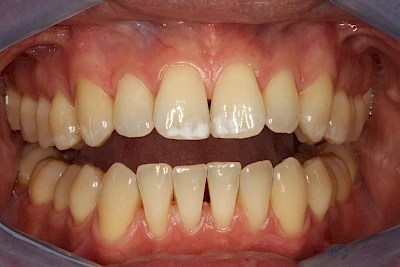

Dunkle bzw. Rötliche Verfärbung

Ist ein einzelner Zahn deutlich dunkler als die Nachbarzähne kann das ein Zeichen sein, dass der Nerv abgestorben ist. Unter Umständen wurde bereits eine Wurzelkanalbehandlung vom Zahnarzt durchgeführt. Eine Abklärung durch den Zahnarzt ist in jedem Fall sinnvoll.